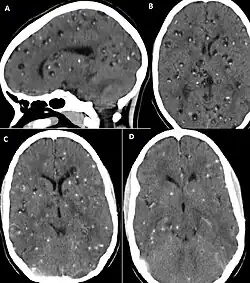

CT scans and magnetic resonance imaging (MRI) give objective information about the number and pattern of lesions, the stage of healing, and how the immune system is responding to the parasites.[19] MRIs are better for evaluating different spatial planes and provides clearer images, which helps in identifying small lesions at the back of the brain or near the skull that may be missed on CT scans. CT scans are more sensitive at detecting calcium buildup in the brain due to its ability detect calcifications in the brain.[30]

Live vesicular cysts are small, round lesions with little swelling around them and do not need contrast for imaging. The tapeworm head (scolex) usually appears as an asymmetric nodule inside the cysts. Multiple live cysts with these heads corroborate the diagnosis. Once the cysts begin to break down (colloid cysts), their borders become unclear, they are surrounded by swelling and exhibit significant ring or nodular contrast enhancement. Calcified cysticerci are shown on CT scans as non-enhancing hyperdense nodules without swelling.[20]